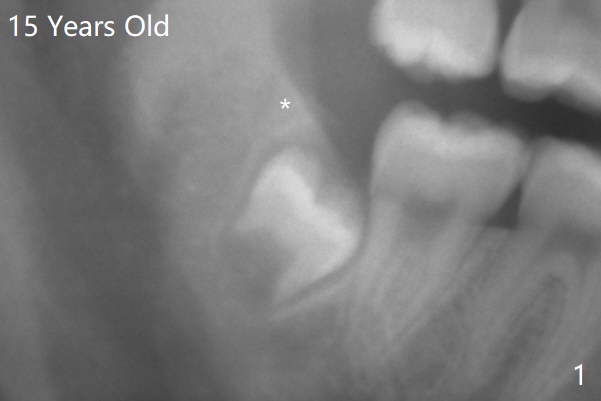

18岁时三角形变大,密度增高(图二)。其实术中发现外斜嵴两侧都不明显(女孩原因?),拔除两侧都需要颊侧去骨。由于左侧智齿颊侧阻生(图三:*),拔除后两侧都放置骨水泥(Bond Apatite,图四:A)促进骨修复,口腔卫生欠缺,可能容易形成牙周炎。